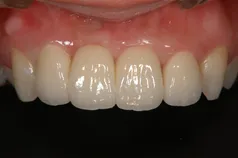

[症例1]

治療前は保険の冠が入っていますが、変色して決してきれいとは言えません。金属も歯茎から透けて見えて黒ずんでいます。

前歯3本を金属を使わないオールセラミック・クラウンで治療し、自然で美しい歯になりました。

ただ白くするのではなく、周りの歯に調和させて自然の歯と見分けがつかず、美しくすることが大切です。

- 治療期間:4ヶ月

- 治療費:30万円

- 治療回数:5回